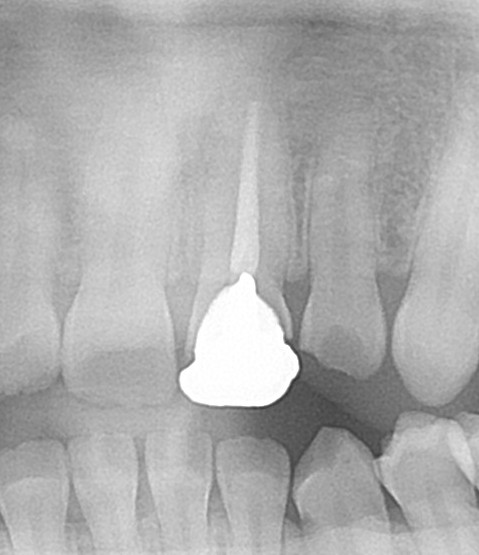

エックス線写真(レントゲン)を確認してみると、

かぶせ物が白く写っています。歯の内部、根っこの中に白いスジが見えますが、これは神経を抜いてお薬が入っている状態です。材料の造影作用で白く写り、神経が取ってあるのが分かります。